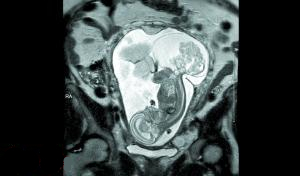

美国德克萨斯州的妇女玛格丽特·伯默怀孕16周时去做常规产检,发现胎儿患上了一种罕见的肿瘤,可能对胎儿构成致命威胁。玛格丽特随后在德州一家医院接受手术,医生打开子宫为胎儿摘除肿瘤,又迅速将胎儿送回子宫并缝合。12周后,宝宝“第二次”出生。

这是玛格丽特的第三个女儿,她已经给宝宝起好了名字,叫琳莉。骶尾部畸胎瘤是一种妊娠期肿瘤,通常长在胎儿的尾骨部分。患病后,肿瘤会和胎儿争抢有限的供血,胎儿心脏跳动就会受到影响,可能会致命。

琳莉23周零5天的时候,玛格丽特在德克萨斯儿童医院接受了手术,这时的肿瘤都快比琳莉大了。手术共进行了5个小时,“摘除肿瘤时我们做得很快,只花了20分钟。较花时间的是打开子宫。我们不想让妈妈的健康受影响,所以进行得很仔细”。

由于肿瘤已经很大,要取出来还是需要切口,摘除肿瘤时胎儿完全离开了玛格丽特的子宫。当时琳莉才大约540克重,在空气中暴露了约20分钟。“所有的羊水也出来了,非常神奇。”卡斯医生说。